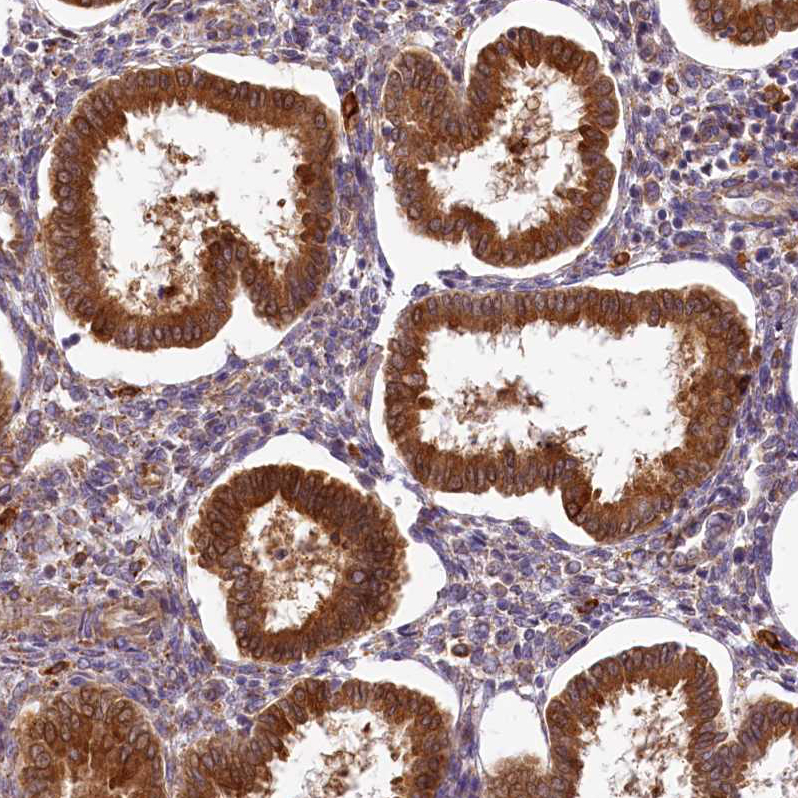

Immunohistochemical staining of human endometrium shows strong cytoplasmic positivity in glandular cells.